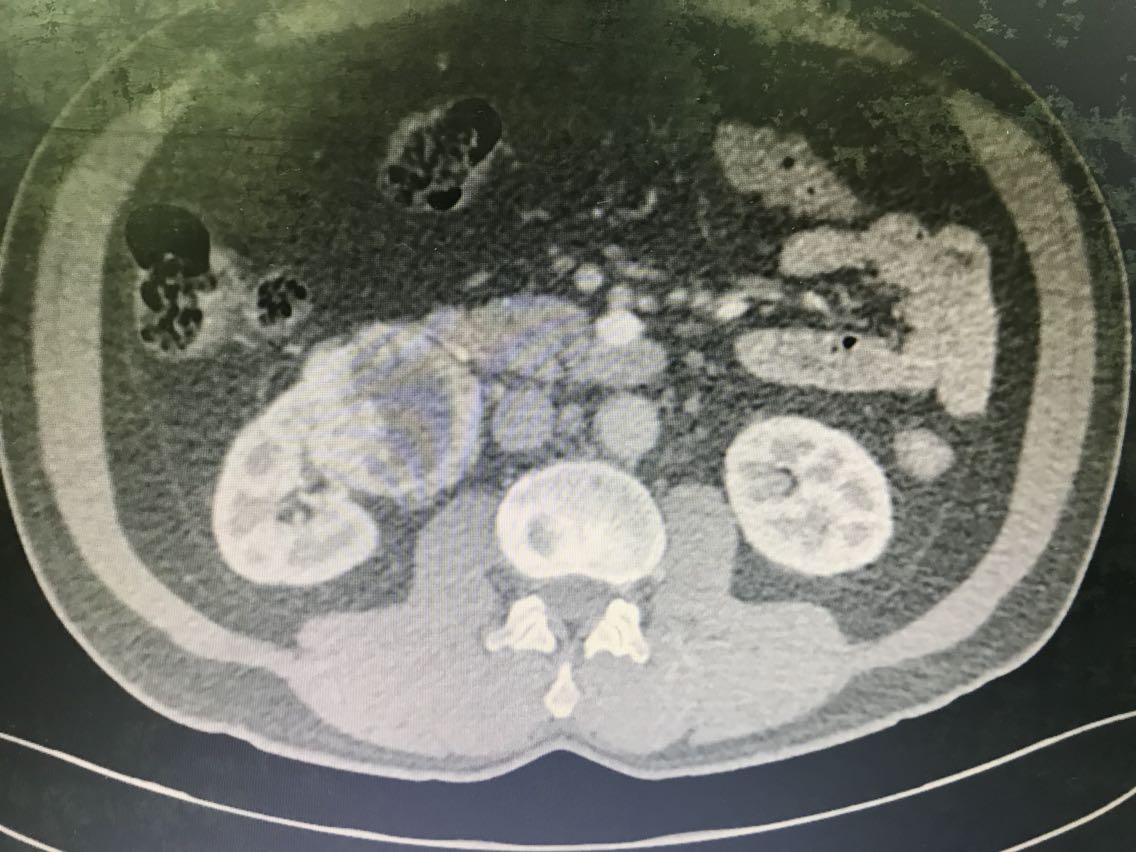

患者男性,62岁。 主诉:咯血、体检发现右肾占位1+月 现病史:1+月前,患者无明显诱因出现反复咯血,为痰中带鲜血,无胃内容物,无畏寒、发热,无胸闷、胸痛,无潮热盗汗,无恶心、呕吐,无腹胀、腹痛等不适。于当地医院就诊,行相关检查(具体报告未见)考虑“支气管扩张”,行相关治疗(具体不详)后患者咯血症状好转出院。患者于住院期间检查发现右肾占位(报告未见),无腰痛、腰胀,无血尿、蛋白尿,无尿少及排尿困难。患者为进一步诊治,于我院门诊就诊,查肝肾功能、肿瘤标志物、小便常规未见明显异常。上腹部增强CT:右肾前下份占位,考虑透明细胞癌(T3aN2Mx),左肾结石、囊肿,腹膜后多发淋巴结,肝脏右后叶下段小囊肿,腹主动脉管壁钙化。现患者为进一步明确诊断及治疗,入住我科。 既往史无特殊。

查体无特殊。 辅助检查: 心电图:窦性心律,电轴左偏,左前分支阻滞,不完全性右束支阻滞。 上腹部增强CT:右肾前下份占位,考虑透明细胞癌(T3aN2Mx),左肾结石、囊肿,腹膜后多发淋巴结,肝脏右后叶下段小囊肿,腹主动脉管壁钙化。

患者术前CT提示右肾肿瘤T3aN2Mx,术中剖视标本见肿瘤未超过肾周筋膜,但最终分期需等待术后病理诊断。可能会出现临床分期过高的情况。